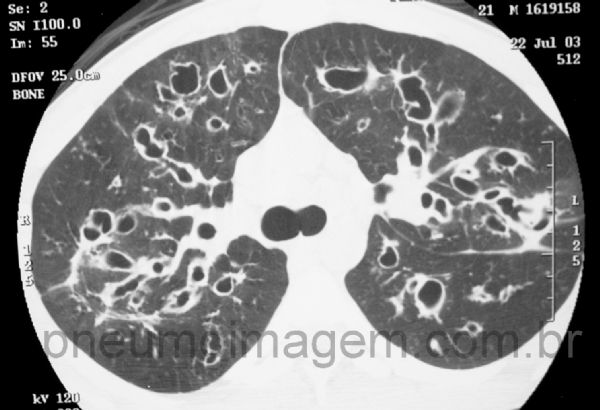

As lesões na FC não se limitam apenas aos lobos superiores, mas estendem-se também aos demais lobos, como pode-se observar neste corte na altura da carina.

The lesions in CF are not limited only to the upper lobes, but also extend to the other lobes, as can be seen in this CT slice at the carina level.